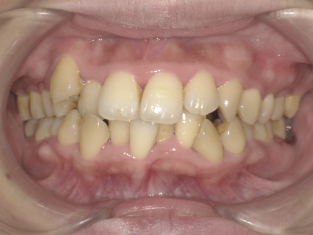

軽度叢生・八重歯症例画像

軽度(少しデコボコしている程度)の方の場合

前歯がほんの少し重なっていたり、八重歯が少しだけ前に出ているといった、“見た目としては気になるけれど重度ではない”タイプです。

この段階であれば、歯が並ぶためのスペースを少し整えるだけで改善できることが多く、非抜歯での矯正が可能なケースがよく見られます。具体的には、歯列の幅をわずかに広げたり、歯と歯の間を少しだけ整えることで、無理なく歯を並べることができます。

治療方法はワイヤー矯正・マウスピース矯正のどちらも選択肢になり、治療期間の目安はお口の状態にもよりますが、比較的短い1年前後で整うケースが多いです。